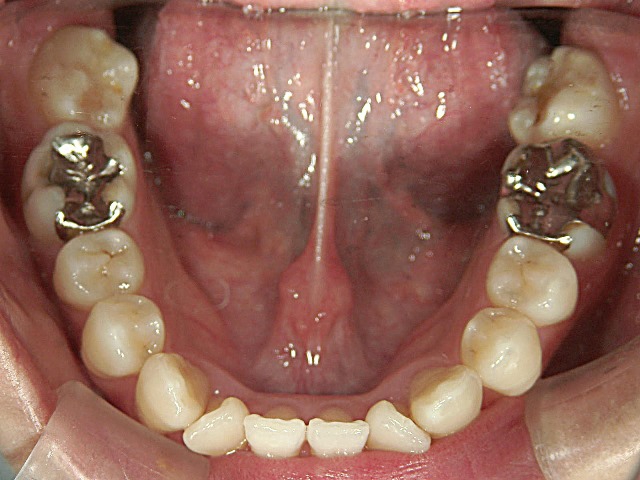

主訴:奥歯で噛んだときに前歯が噛み合わない

中学生になり第二大臼歯が生えてから、真ん中の前歯2本が出てきて、八重歯も目立つようになりました。はじめは八重歯がチャームポイントだと捉えて気にしていませんでしたが、年々歯並びが悪化している気がしました。そのうち前突が原因で口が閉じづらく、寝ている時は口呼吸になってしまいました。

高校時代には、歯並びを改善しようと様々な矯正サイトを閲覧し、自分自身が開咬であることを知りました。開咬とは、上下の歯を噛み合わせた時に前歯に隙間ができることを言います。そういえば、麺を前歯で噛みきること、ハンバーガーにガブッと噛みつくことができませんでした。

その後、伊藤歯科医院に入社し、やっと矯正をする機会に恵まれました。矯正しているのが目立ちにくい治療を希望し、舌側ワイヤー矯正に挑戦することになりました。

出っ歯や八重歯などの歯並びの悪さばかりが気になっていましたが、開咬には前歯で物が噛みきれない、しゃべるときに息が漏れるなどの症状の他に、奥歯ばかりに負担がかかる為、歯の寿命を縮めてしまう可能性がありました。矯正で改善することができて本当によかっと思います。みなさんも歯並びで気になることがあったら、気軽に相談してみてくださいね。